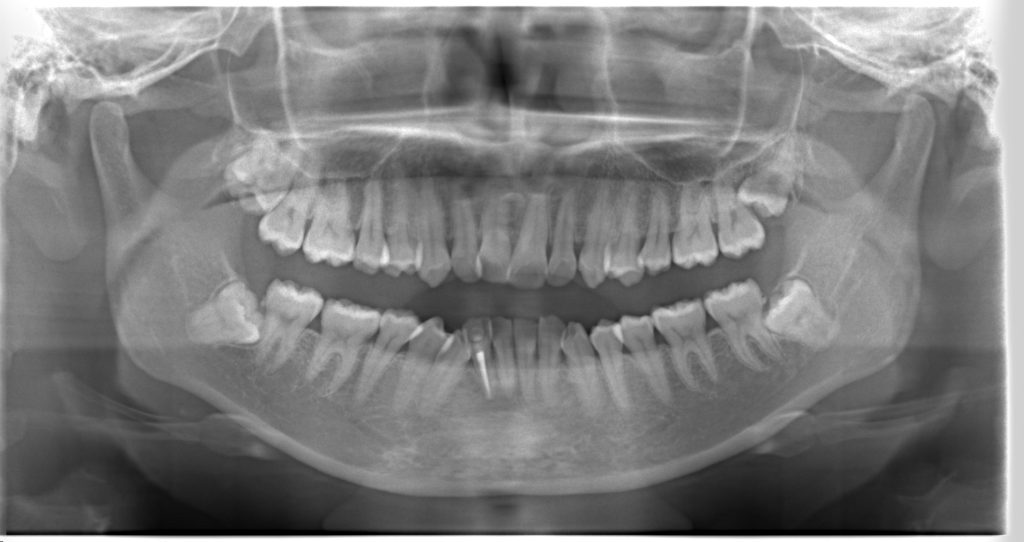

受け口の状態により、上の歯が内側に入り込み、反対の噛み合わせになっている部分が見られました。見た目の問題だけでなく、噛み合わせのバランスにも影響を与えていました。

当院では、精密検査(55,000円)にて、見た目だけではなく、骨・歯・咬合の関係を総合的に評価します。矯正治療にあたって抜歯が本当に必要なのか、どの程度まで非抜歯矯正で機能性を保てるのかは、一人ひとりの状態によって判断が変化します。

- 前歯部交叉咬合を伴う不正咬合

- ゴムメタルワイヤー矯正

- 2024年9月6日(10ヶ月)